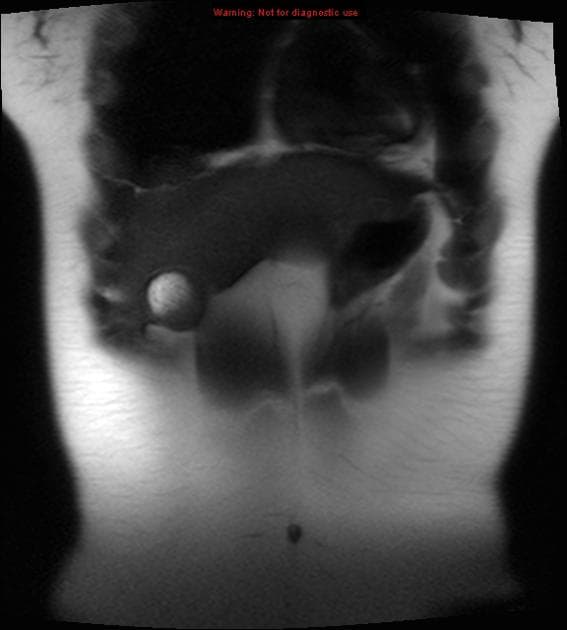

U nang ống mật chủ type III (Choledochocoele)

U nang ống mật chủ type III (Choledochocoele) trên hình ảnh chụp đường mật trong mổ và CT.

- Làm mờ hệ thống đường mật kèm giãn ống mật chủ ngoài gan.

- Giãn ống mật chủ ngoài gan trong thành tá tràng, trong lòng có sỏi.

- "Choledochocoele là dạng hiếm của u nang ống mật chủ type III, đặc trưng bởi giãn dạng nang đoạn ống mật chủ trong thành tá tràng."